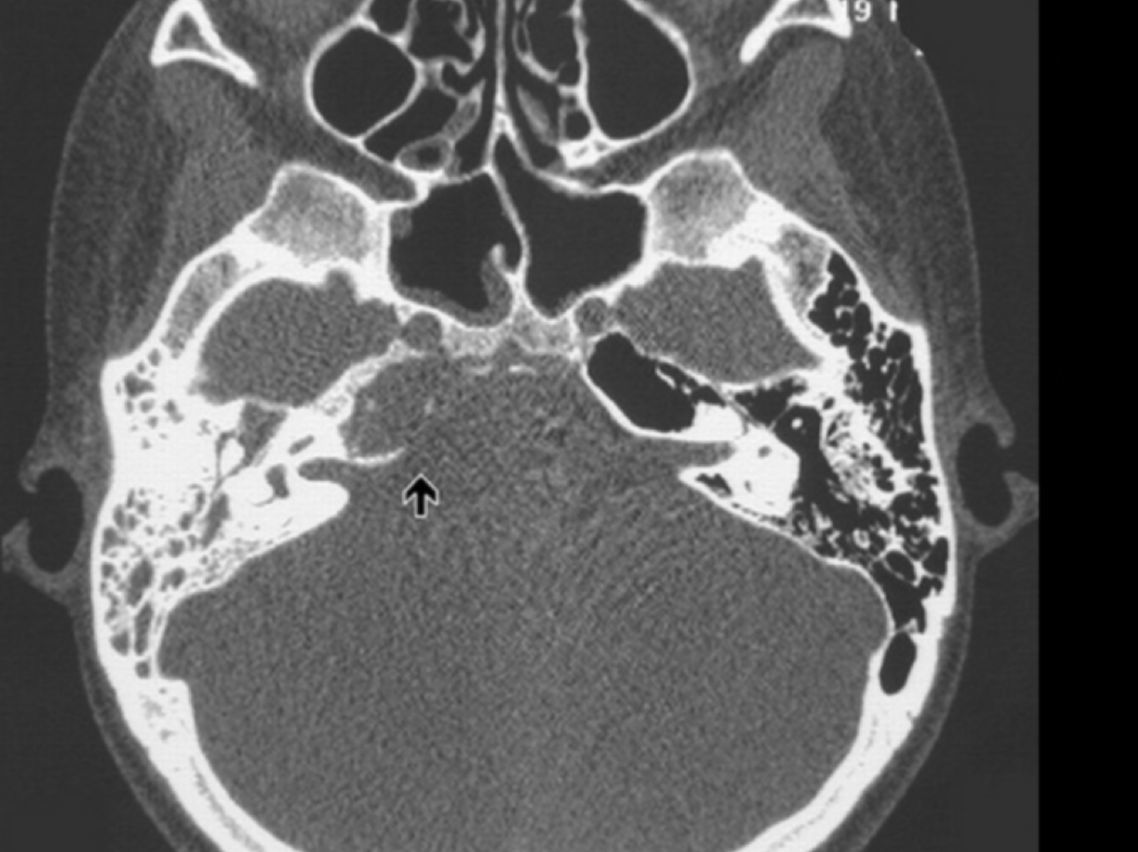

¿Cuáles son las pistas diagnósticas en la TC de la otitis media?

¿Cuáles son los hallazgos radiológicos en la TC de mastoiditis?

¿Cuál es una pista característica del colesteatoma?

Destruye hueso